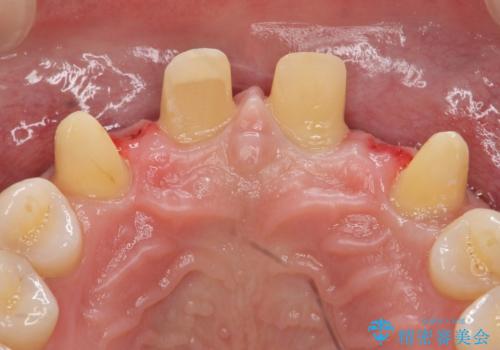

- 前歯部のすきっぱと歯並びが気になるので診て欲しいといらっしゃった方の症例です。

全顎矯正は御希望されなかったため、上顎前歯部のみの部分矯正とオールセラミッククラウンによる補綴を行いました。

- オールセラミッククラウン…¥100,000×6、仮歯…¥10,000×6、部分矯正…¥200,000費用は治療当時の料金となります